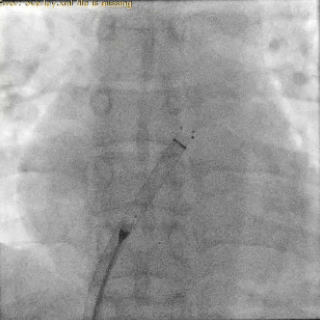

释放封堵器

DSA下封堵器完全释放后形态

封堵器释放后双盘紧贴间隔